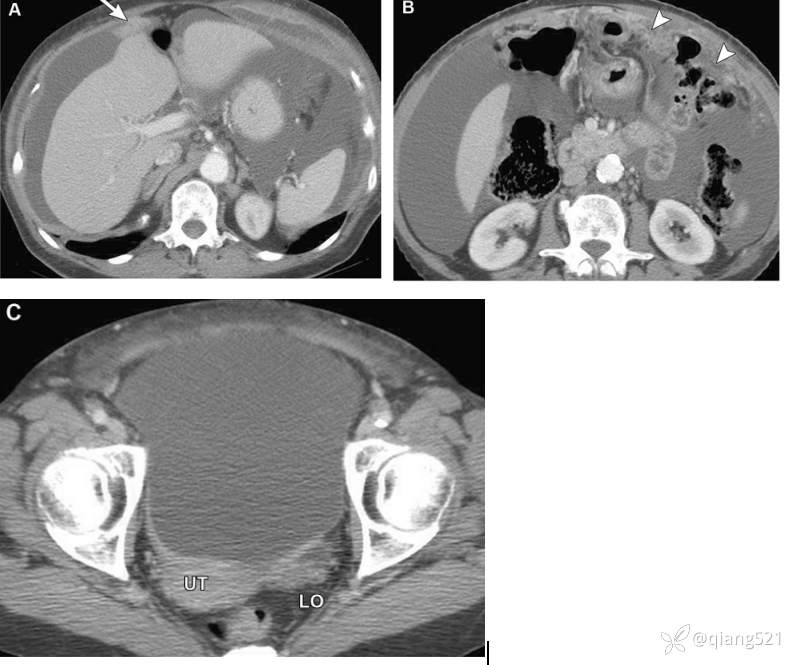

一例43岁女性左卵巢成熟畸胎瘤切除术后腹膜胶质瘤病。A、B经腹部的轴向CECT显示腹膜肿块样增厚(箭头)和复杂的腹腔内积液,导致肝缘呈扇形(箭头)。